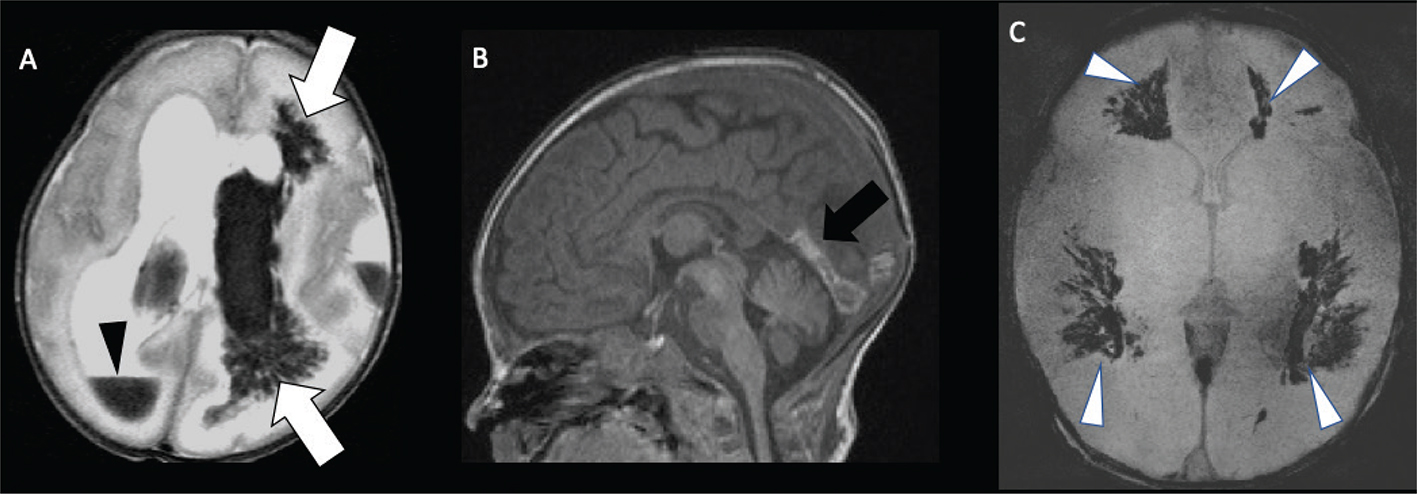

Acute phases of fetal stroke, such as in case of congenital heart disease or twin-twin transfusion syndrome (TTTS), may only rarely be detected prenatally. Fetal stroke often manifests with the chronic features of unilateral ventriculomegaly and volume loss with or without associated hemorrhage (Figures 1 and 2).

Fig 1

Figure 1. Acute and chronic fetal infarctions. 29 weeks of gestation fetus with a chronic stroke in the right hemisphere. (A) Axial HASTE (Half Fourier Singleshot Turbo Spin-Echo) and (B) Gradient Recall Echo (GRE) images showing unilateral enlargement of the right lateral ventricle, with periventricular white matter loss (white arrow) and linear blood staining (black arrowhead). 21 weeks of gestation fetus with congenital heart disease with acute stroke in the right hemisphere. (C) Axial DWI and (D) ADC map showing areas of reduced diffusion in the left ACA and MCA territories (black arrow) with questionable infarct in the right MCA territory (white arrowhead). Case courtesy of Dr. Tamara Feygin, Department of Radiology, Children’s Hospital of Philadelphia.

Fig 2

Figure 2. Three-day-old girl with chronic encephalopathy. Pregnancy complicated by maternal HELLP (H: Hemolysis, EL: elevated liver enzymes, LP: low platelet count) syndrome. Sagittal T1- (A) and coronal T2-weighted images (B) show microcephaly and bilateral chronic MCA-territory infarctions. Case courtesy of Dr. Tamara Feygin, Department of Radiology, Children’s Hospital of Philadelphia.